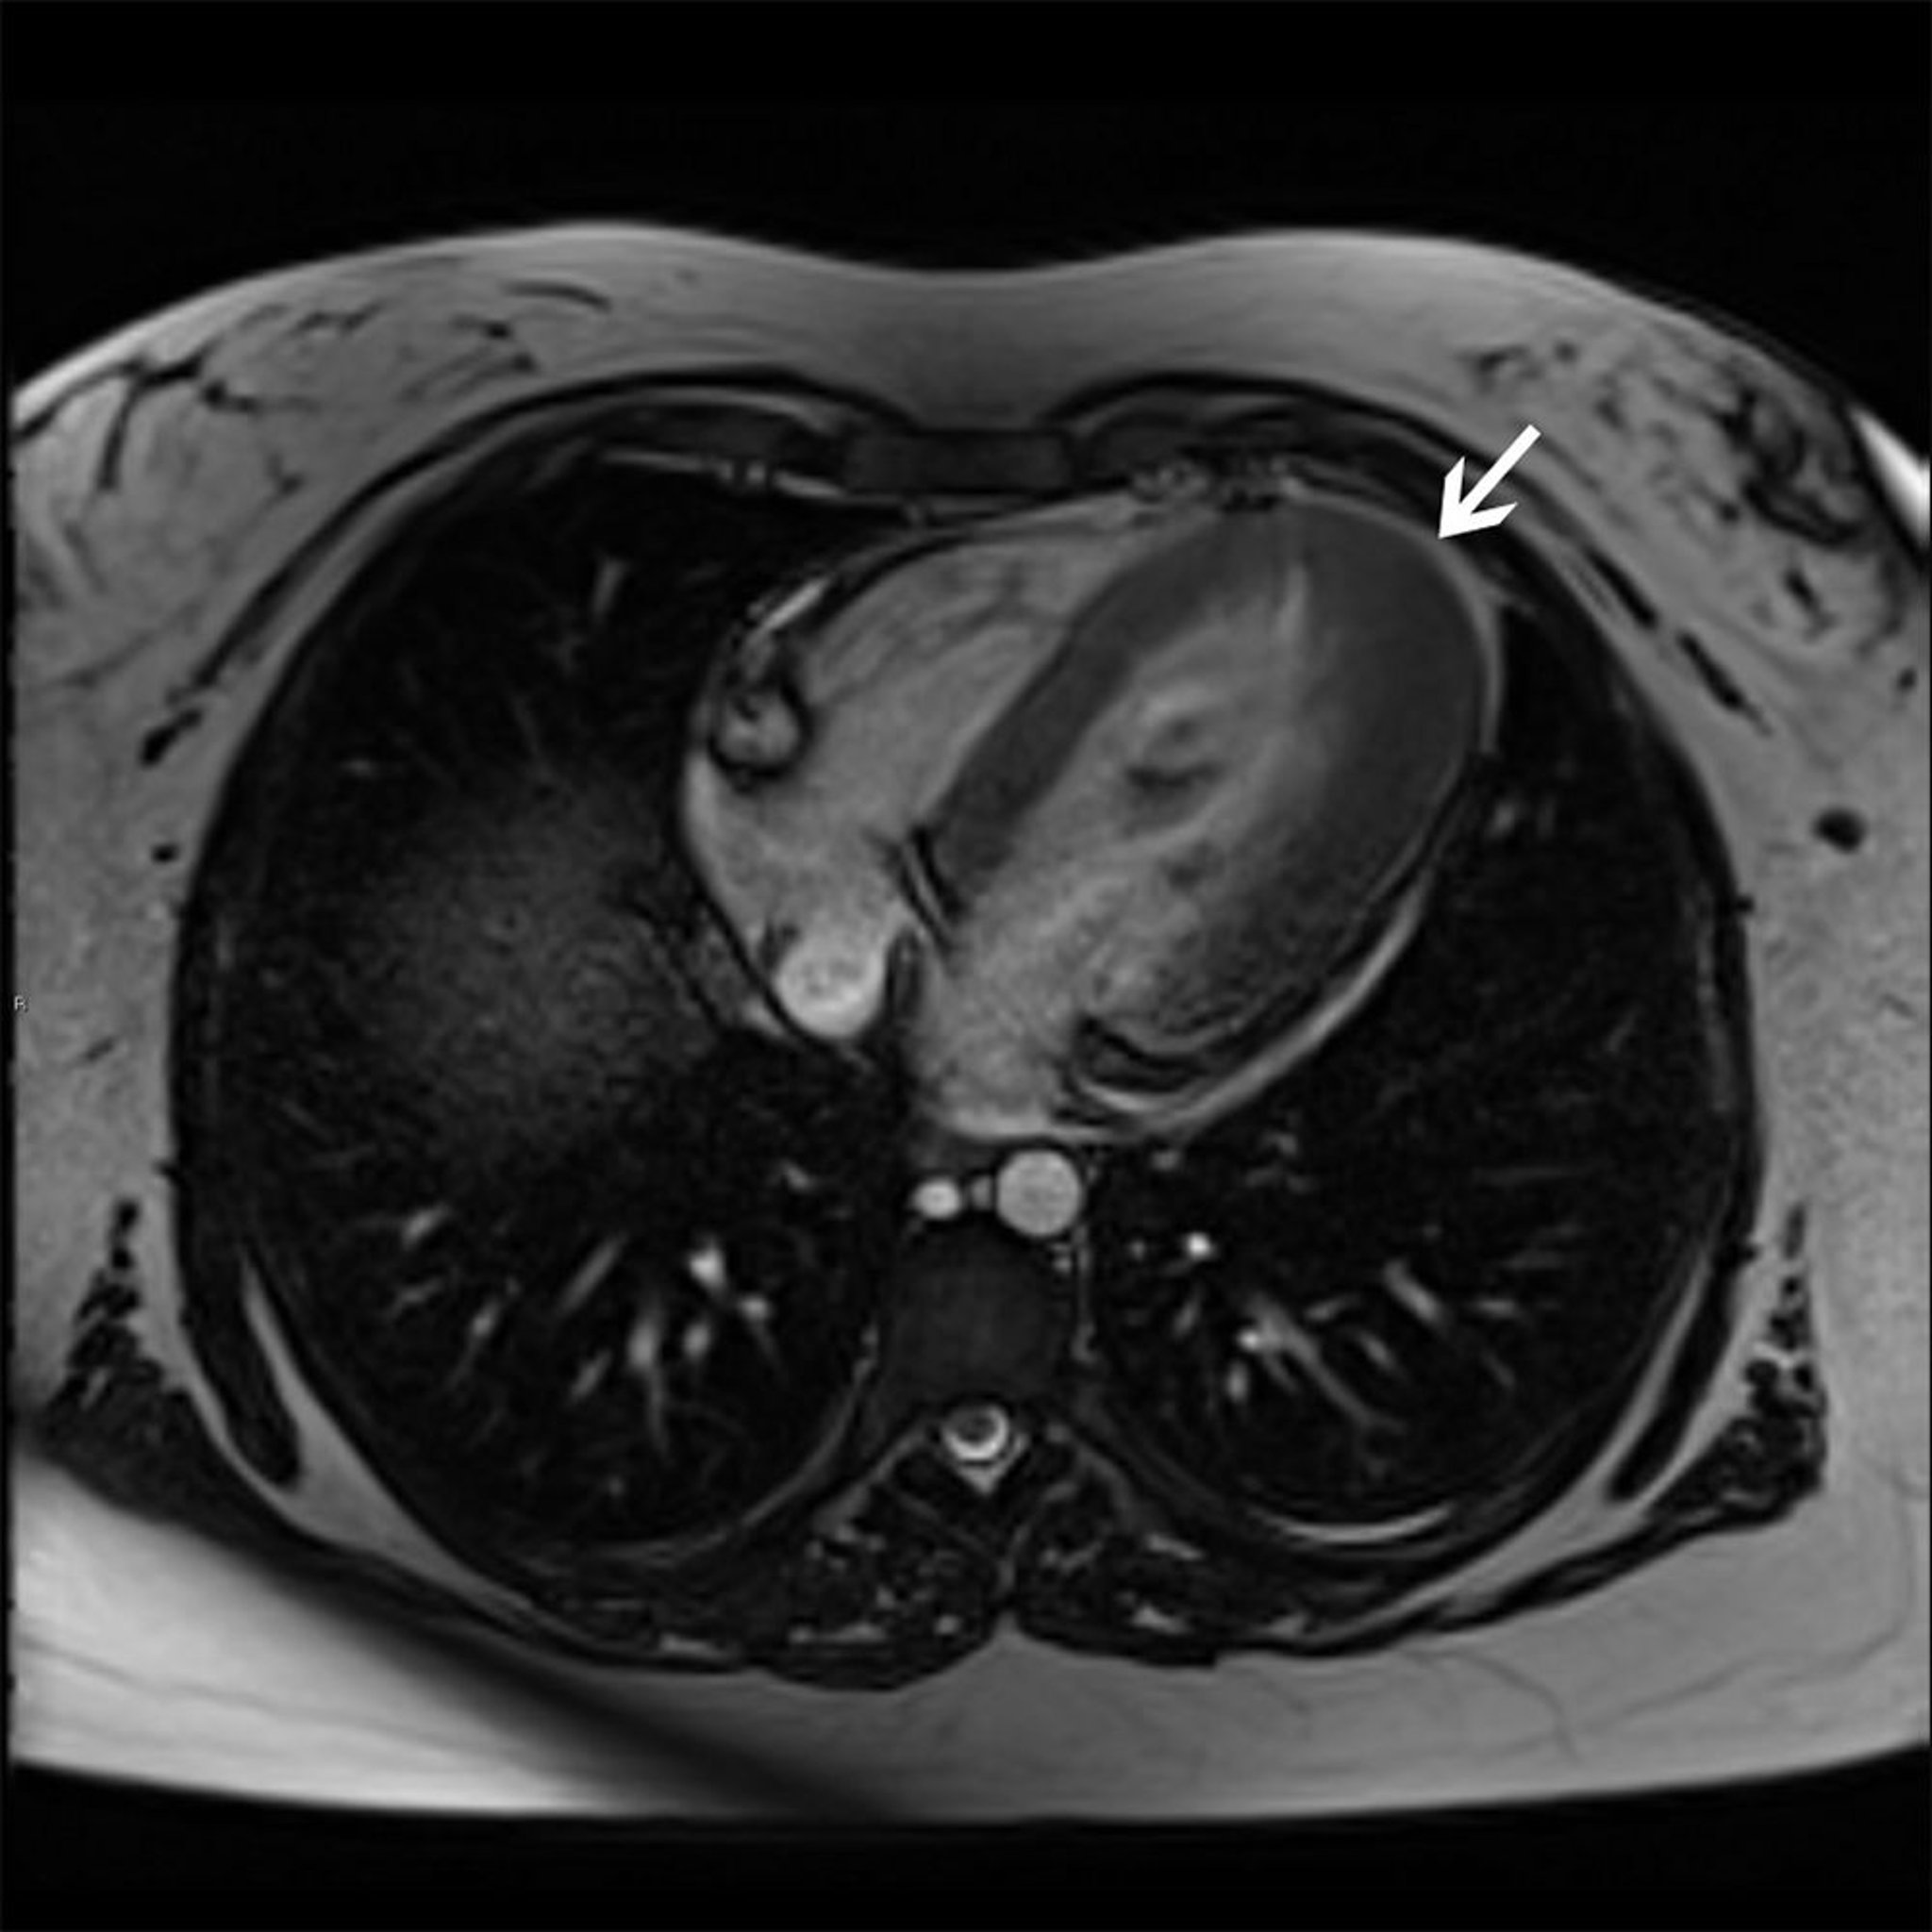

ECG and 2-dimensional echocardiography and/or MRI (the best noninvasive confirmatory tests) are done. Chest x-ray is often done but is usually normal because the ventricles are not dilated (although the left atrium may be enlarged). Exercise testing and 24-hour ambulatory monitoring may be helpful for patients considered at high risk, although accurately identifying such patients is difficult. Patients with syncope or sustained arrhythmias should be evaluated as inpatients.

• Delayed enhancement on cardiac MRI

• Extensive and diffuse late gadolinium enhancement on MRI

• Echocardiography is done, but, if available, MRI best shows the abnormal myocardium.